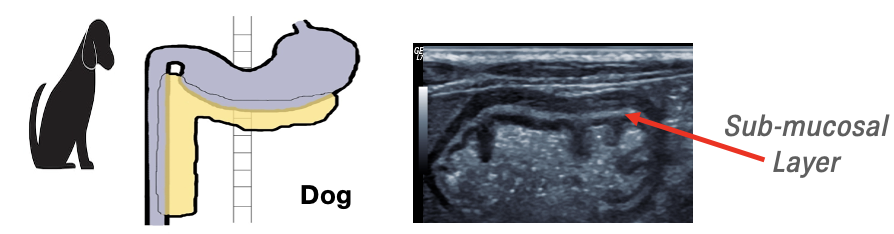

The lie of the stomach and position of the pylorus varies in the canine and feline patient and this will be particularly noticeable when assessing the gastric outflow tract. Also, the long axis of the stomach in dogs lies more horizontal, across the spine and patient midline, whereas in cats it lies more vertical and parallel to the spine and to the left of the patient midline.

In the canine patient, the pyloroduodenal junction and cranial duodenal flexure are more lateral in position when compared to the feline patient.

Canine gastric submucosal layer is thin in dogs (as seen in the small intestines), however in cats the submucosal layer is prominent and hyperechoic in the fundic region secondary to fat deposition

In dogs, the transition from pyloroduodenal angle to proximal duodenum is prominent when compared to cats

Magnified view of normal gastric wall layer architecture